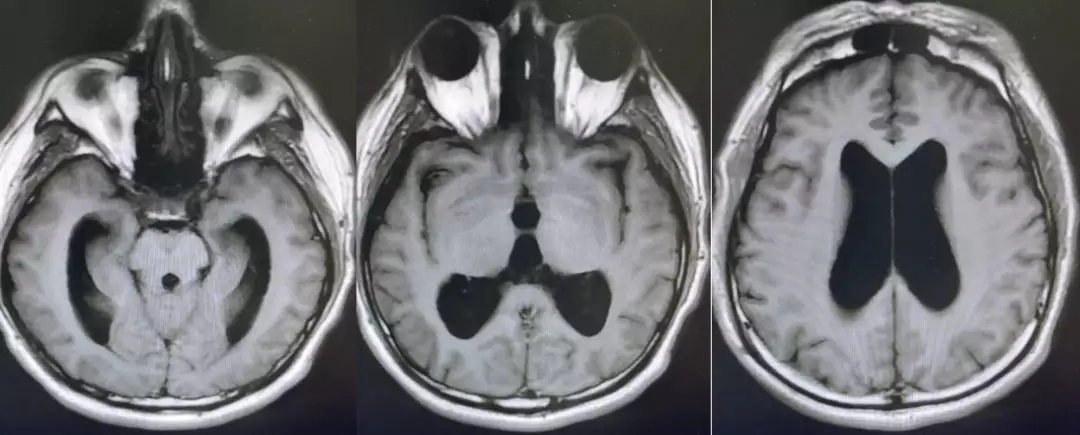

颅脑核磁T1W1成像

颅脑核磁T2W1成像

颅脑核磁平扫加增强扫描:

第四脑室内见一巨大形态不规则的异常信号影,肿瘤信号不均匀,T1W1呈略低信号影,T2W1呈稍高及高信号影,增强扫描可见肿瘤不均匀明显强化。肿瘤充满整个四脑室,大小约44*37*55mm,上方接近四脑室顶部,下方至颈2脊髓平面上方,已经部分侵袭桥脑、延髓,局部边界不清,无明显间隙,脑干局部明显受压变形。肿瘤上方脑室系统扩张,出现梗阻性脑积水征象。

影像诊断:1.第四脑室内占位性病变,室管膜瘤可能性大;2.梗阻性脑积水。